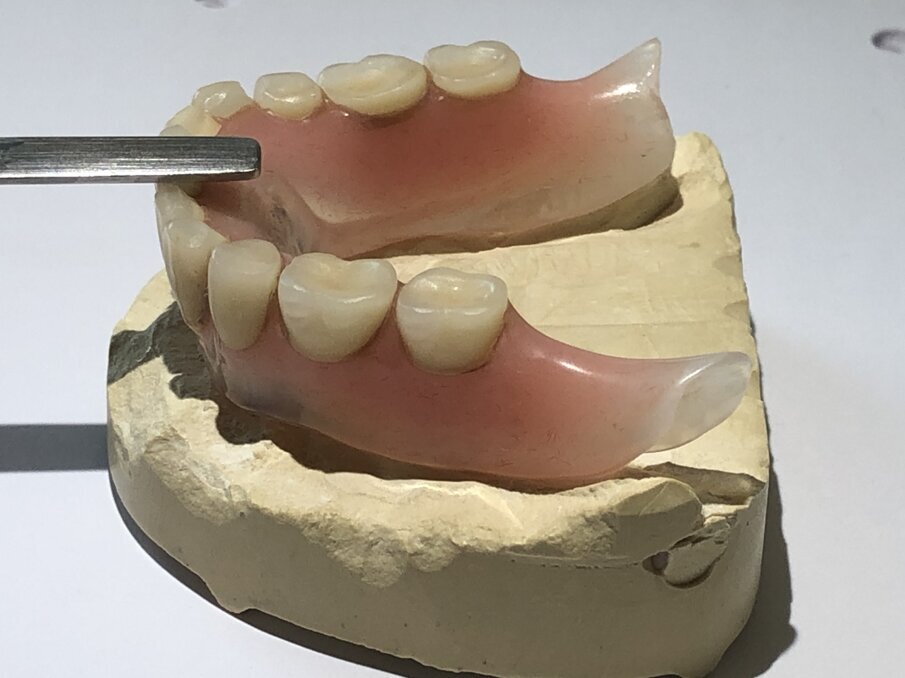

De foto’s van de dolderstaaf in deze publicatie zijn afkomstig van een patiënt, waarvan wij de constructie hebben vernieuwd wegens onvoldoende houvast. Om de dolderstaafconstructie eenvoudiger en sneller in de productie te vervaardigen, wordt vaak een nauwkeurig secundair onderdeel in de prothese achterwege gelaten. Dit betekent dat de huidige prothese zonder precisiebasis wordt geslepen en de dolderstaaf in de prothese wordt gepolymeriseerd zonder een geschikt secundair onderdeel (afbeelding 1, 2, 3, 4 en 5).

Dit heeft echter twee grote nadelen: de minimale houd- en hoge schudbeweging van de prothese (vooral met twee implantaten) vanwege het ontbreken van precisiedelen (afbeelding 6 en 7). Dit betekent dat er niet kan worden voldaan aan de verwachtingen van de patiënt, om na de implantaatbehandeling een stabiele prothese te ontvangen.